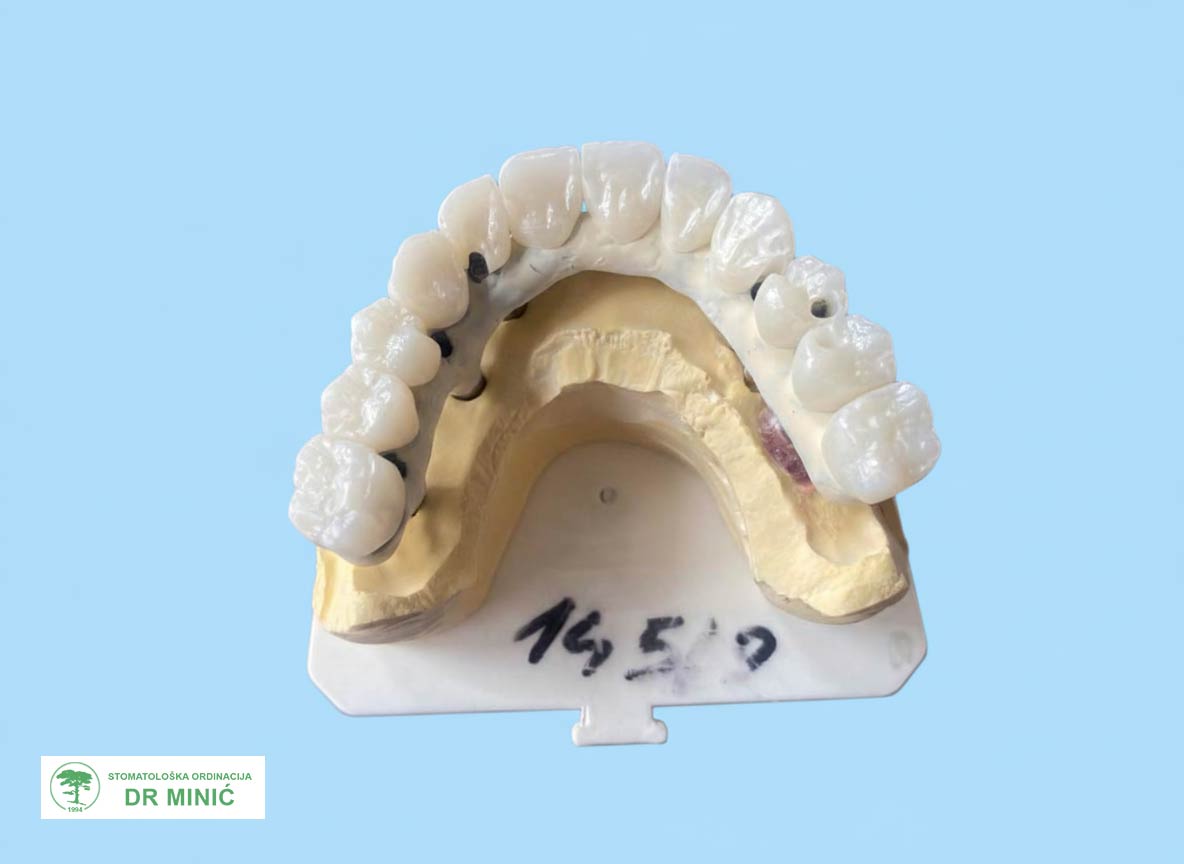

Treća faza – izrada trajnog rada

Nakon četri meseca započeta je izrada trajnog protetskog rada:

• Uzet je precizan otisak vilica.

• Napravljen je plastični model budućih zuba, koji je poslužio za procenu izgleda i funkcije.

• Zatim je urađena metalna (titanijumska) konstrukcija (prečka) na koju su kasnije postavljeni zubi.

• U više proba proveravani su izgled, položaj i stabilnost rada.

• Na kraju je izrađen završni rad sa maskom koja imitira desni i sve je cementirano u ustima.